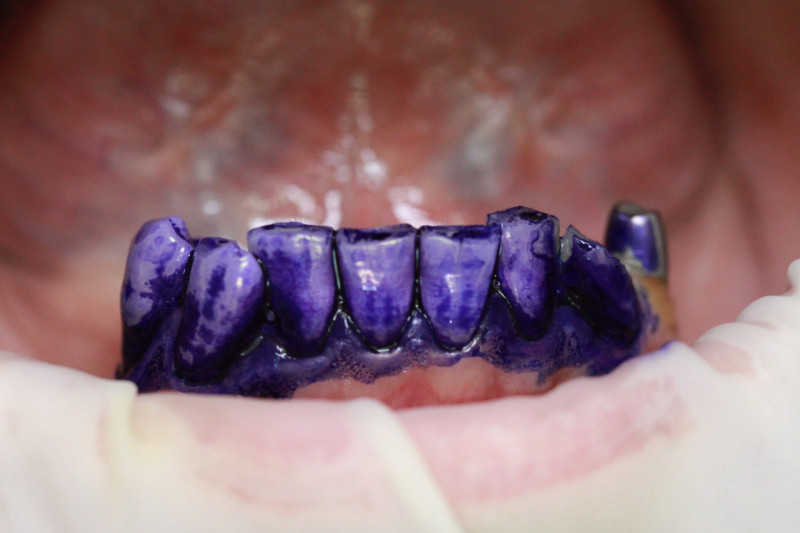

Index Dual работает по принципу селективного окрашивания: свежий налёт (до 24 часов) становится розовым, а зрелый кариесогенный налёт (более 24 часов) — синим.

• Для пародонтологов: Чёткая дифференциация старого налёта (синий цвет) указывает на зоны риска развития пародонтита и локализацию патогенной флоры.

• Чёткая контрастность: Синий цвет настолько интенсивный, что его невозможно спутать с естественной пигментацией или гиперемией дёсен.